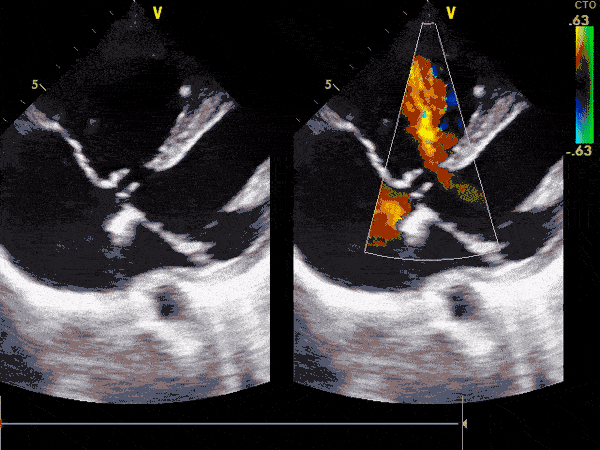

Ekokardiografia transtorakale triplex (2D, color, doppler) ose e njohur ndryshe si eko e zemrës. Ky është ekzaminimi bazë dhe i domosdoshëm për të diagnostikuar këto sëmundje.

Pamje të kapura me TTE:

Me anë të TTE-së vëzhgohen shumë mirë vrimat në zemër, duke përfshirë:

• Pozicionin e tyre.

• Madhësinë.

• Ndikimin në madhësinë dhe funksionimin e zemrës.

Me anë të TTE-së mund të vëzhgohen dhe të vlerësohen:

• Valvulat e zemrës.

• Enët e gjakut që dalin nga zemra.

• Enët e gjakut që hyjnë në zemër.

Nga rezultati i TTE-së varet edhe trajtimi i mëtejshëm i fëmijës. E rëndësishme është se sa më shpejt të diagnostikohet një sëmundje e lindur e zemrës aq më efikas është dhe trajtimi.